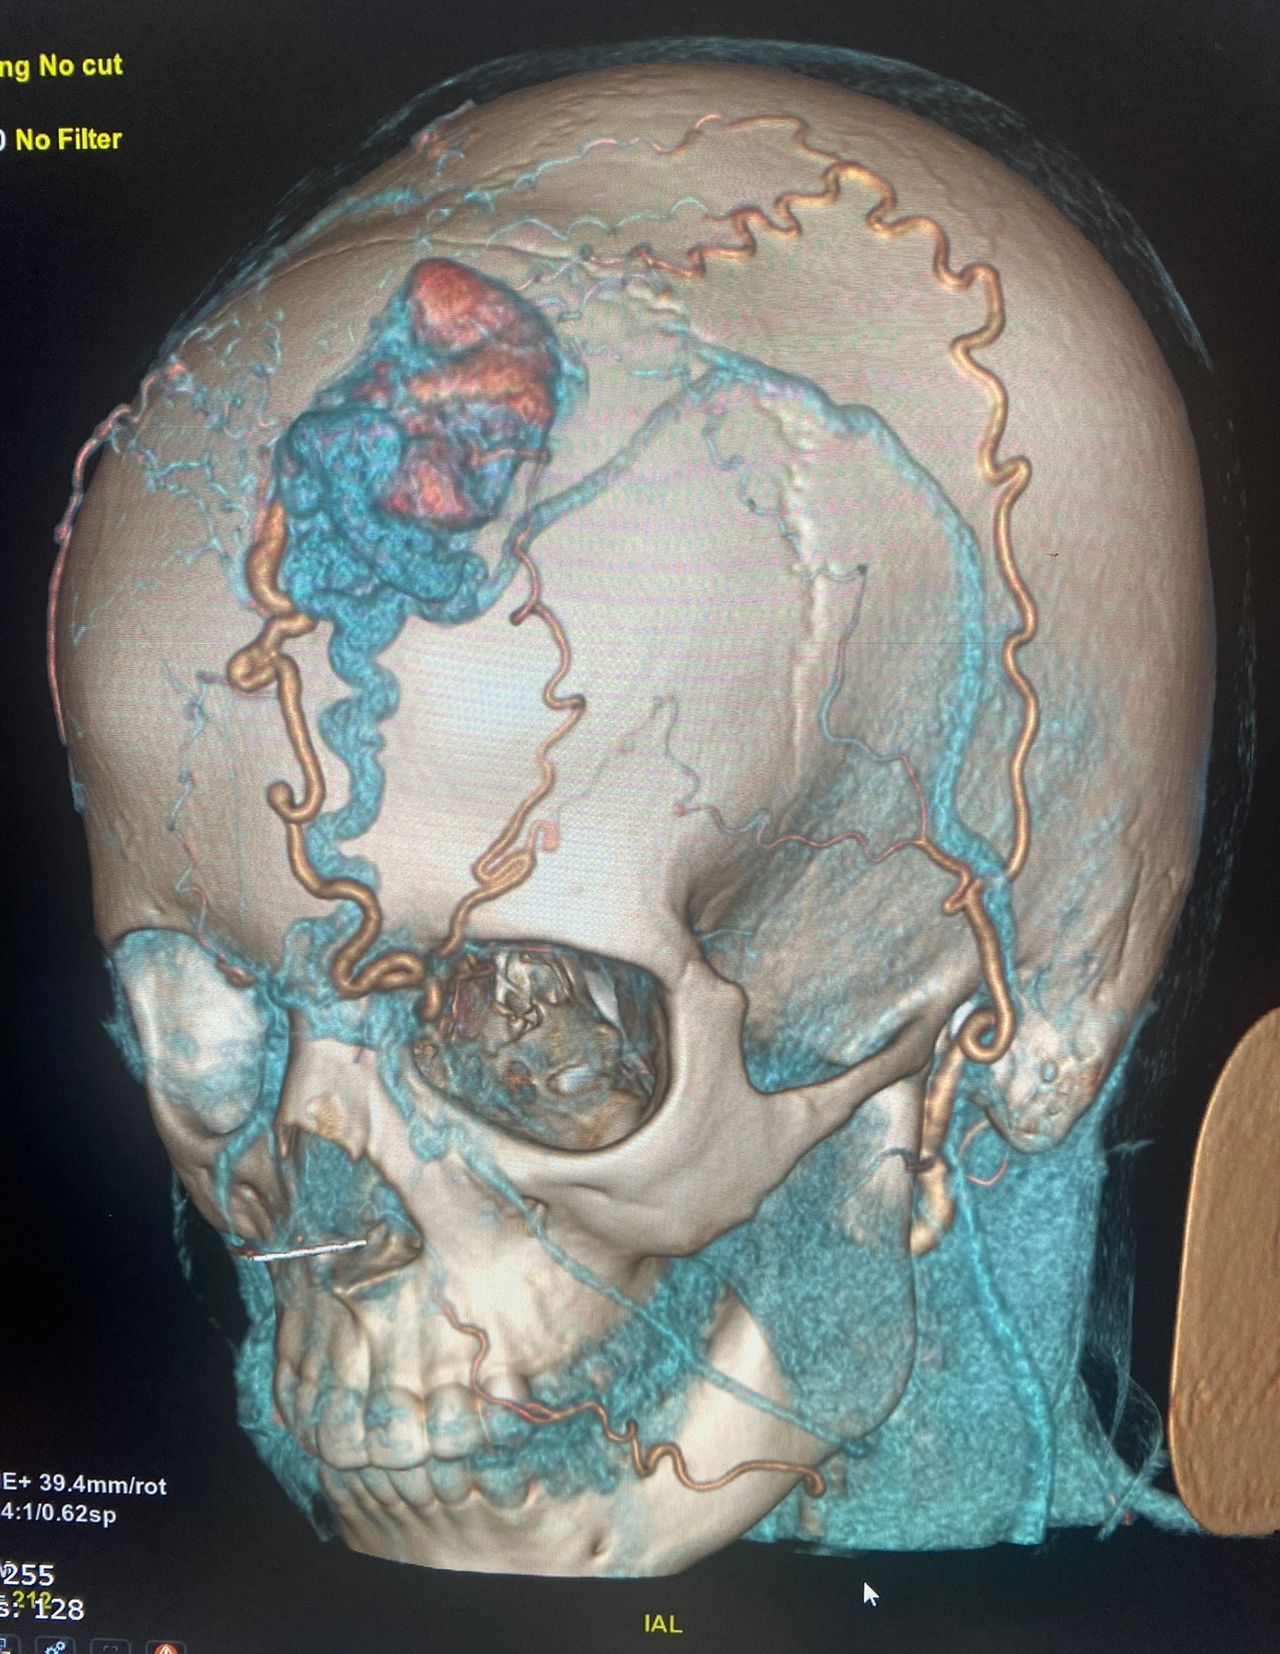

Foto e video